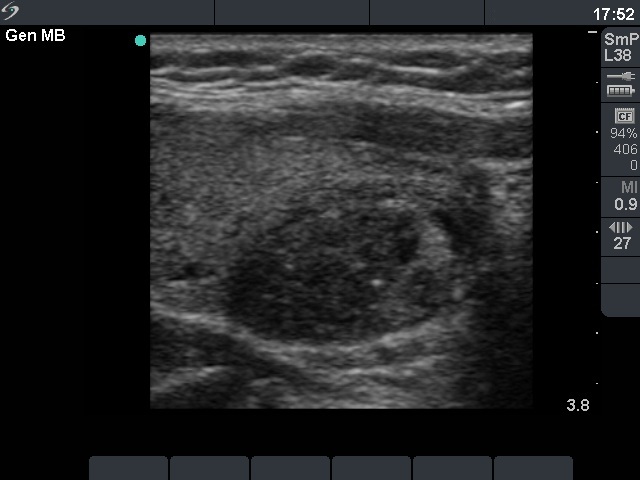

Clinical presentation: a 40-year-old woman was sent for ethanol sclerotherapy. Her thyroid cyst was evacuated three times but after each occasion the cyst got refilled within a week. FNAC resulted in a benign cystic lesion.

First row: before the first session of sclerotherapy. There was a cystic nodule in the left lobe with the dimensions of 32x27x42 mm (width x depth x length). 5 sessions of ethanol sclerotherapy was administered.